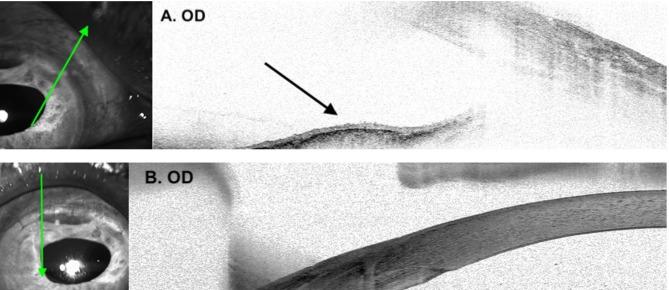

A 74-year-old Chinese man underwent extracapsular cataract extraction in his right eye and developed a translucent iris membrane 4 months later. He was treated with two intracameral 5-FU injections and membranectomy at 2 weeks apart. At one year following the second membranectomy, the patient maintained a clear cornea without residual or recurrent membrane, an endothelial cell density of 1072 cell/mm, a visual acuity of 20/50 and a normal intraocular pressure. Our technique of using dispersive and cohesive viscoelastics in protecting the corneal endothelium from intracameral 5-FU, helped preserve corneal endothelial cells and maintain corneal clarity at one year after surgery.

一位 74 岁的中国男性在右眼接受了囊外白内障摘除术,4 个月后出现半透明虹膜膜。他在相隔 2 周的时间内接受了两次眼内 5-FU 注射和膜切除术。第二次膜切除术后一年,患者角膜透明,无残留或复发的膜,内皮细胞密度为 1072 个细胞/mm,视力为 20/50,眼压正常。我们使用分散和粘性粘弹剂的技术来保护角膜内皮免受眼内 5-FU 的影响,有助于在手术后一年保持角膜内皮细胞并保持角膜透明度。